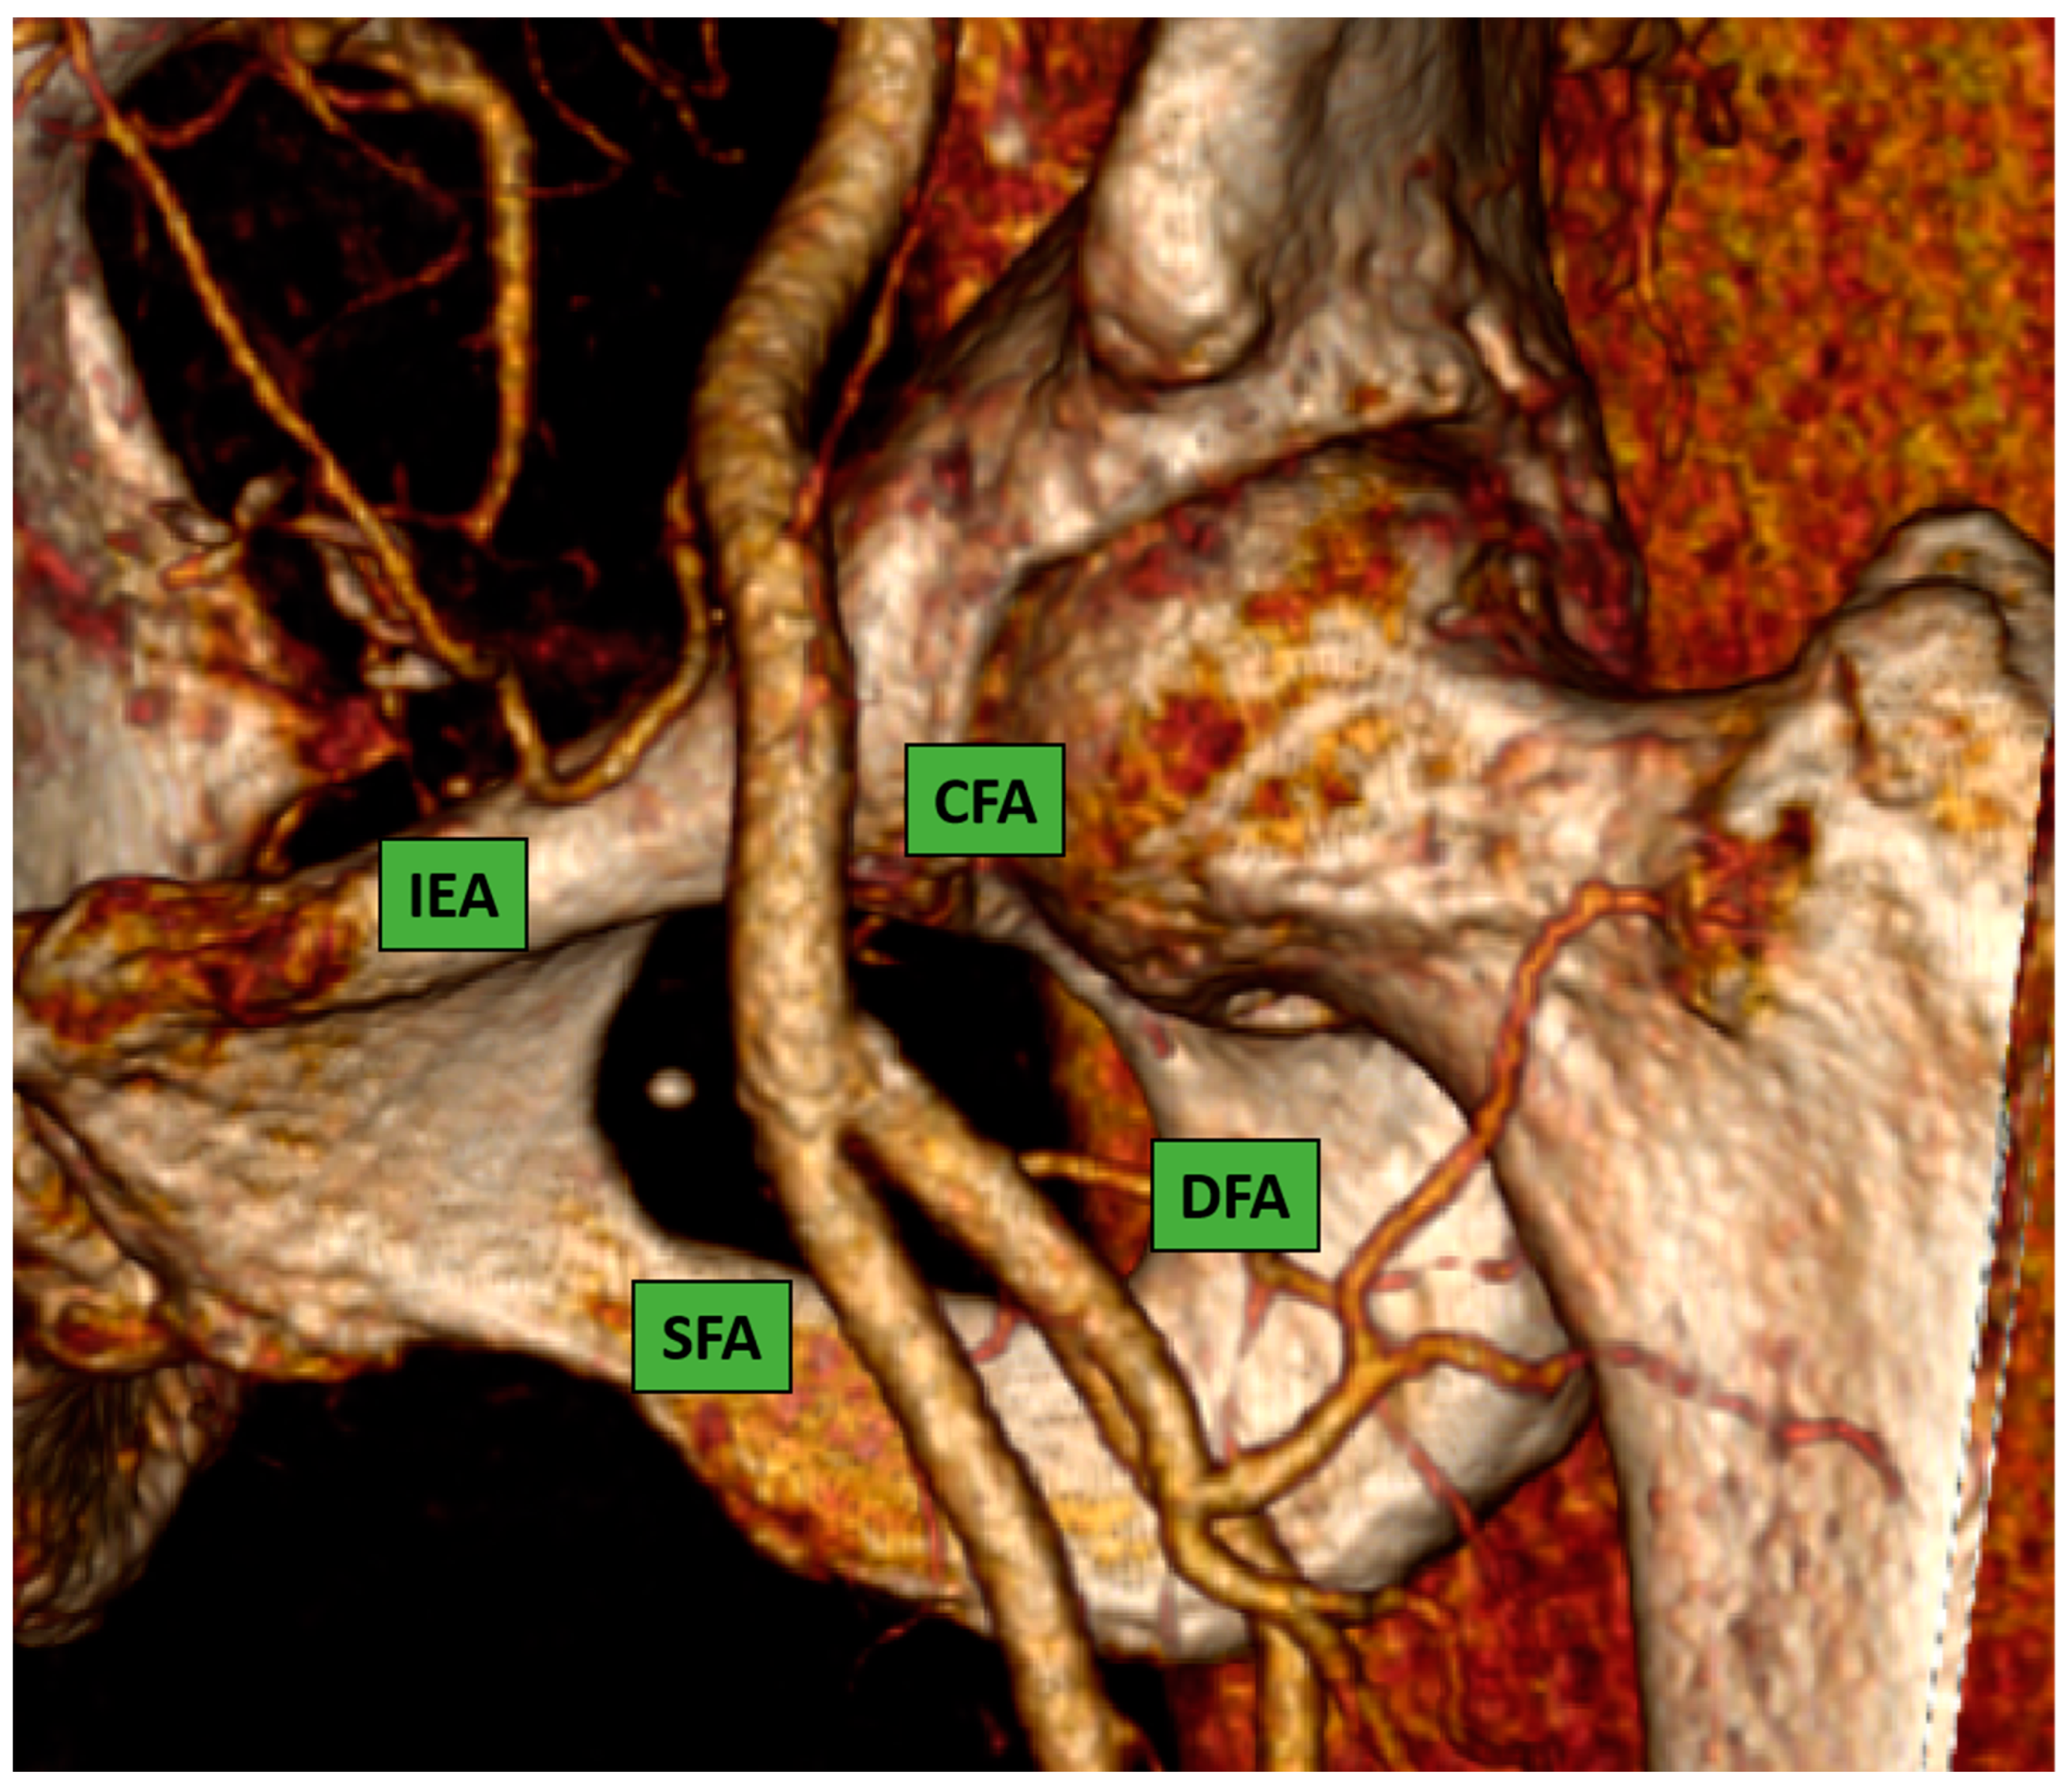

- Fluoroscopy: CFA position can be determined by using anatomic landmarks with pulsation and fluoroscopic guidance. The puncture should be performed with consideration of a “safe zone” in the segment of the CFA extending between the inferior epigastric artery and the distal portion of the CFA, ideally 1 cm above the femoral bifurcation, corresponding to the space between the inferior edge and the middle part of the femoral head. This approach might avoid the puncture below the bifurcation (occurring below the middle third of the femoral head in 95% of patients [9]) in order to avoid pseudoaneurysm and it might avoid even puncture below the emergency of inferior epigastric (occurring usually above the middle third of femoral head).In order to minimize and avoid complications occurring after the puncture, it is mandatory to identify landmarks for the dermotomy and arteriotomy site.The inguinal ligament is the anatomical landmark that separates the external iliac artery from the CFA.

- Angiography-guided femoral puncture: A secondary access is necessary (radial or femoral) for the possibility of reaching the proximal part of the CFA to perform digital subtraction angiography (DSA) and road mapping Figure 3 to guide the puncture.